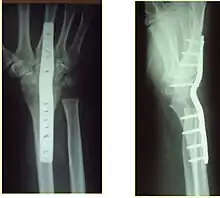

If the fractures are unlikely to be reduced by closed means, open reduction with internal plate fixation is preferred.[4] Although major complications (i.e. tendon injury, fracture collapse, or malunion) result in higher reoperation rates (36.5%) compared to external fixation (6%), ORIF is preferred, as this provides better stability and restoration of the volar tilt.[4][20] Following the operation, a removable splint is placed for 2 weeks, during which time patients should mobilize the wrist as tolerated.[4]